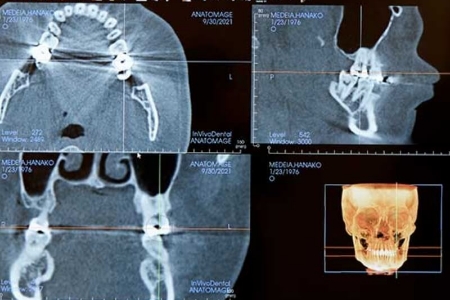

歯科用CT(Computed Tomography)とは、エックス線を利用し、コンピューター処理することによって、物体の内部を立体的(3D)に撮影する技術です。 歯科用CTであごの骨の量や質、周囲を通る血管や神経の位置などを正確に把握したうえで、手術をシミュレーションしてより安全で確実な治療計画を立てることができます。当院の歯科用CTは、 「KaVo社製 OP 3D Vision」を導入しています。

インプラント治療を安全に行うためには、事前検査はとても大切です。患者さんのあごの骨や周囲の組織の状態を詳細に検査して、より安全な治療計画を立てます。検査内容としては、歯科用CT撮影、口腔内写真、歯周病検査、模型検査などになります。